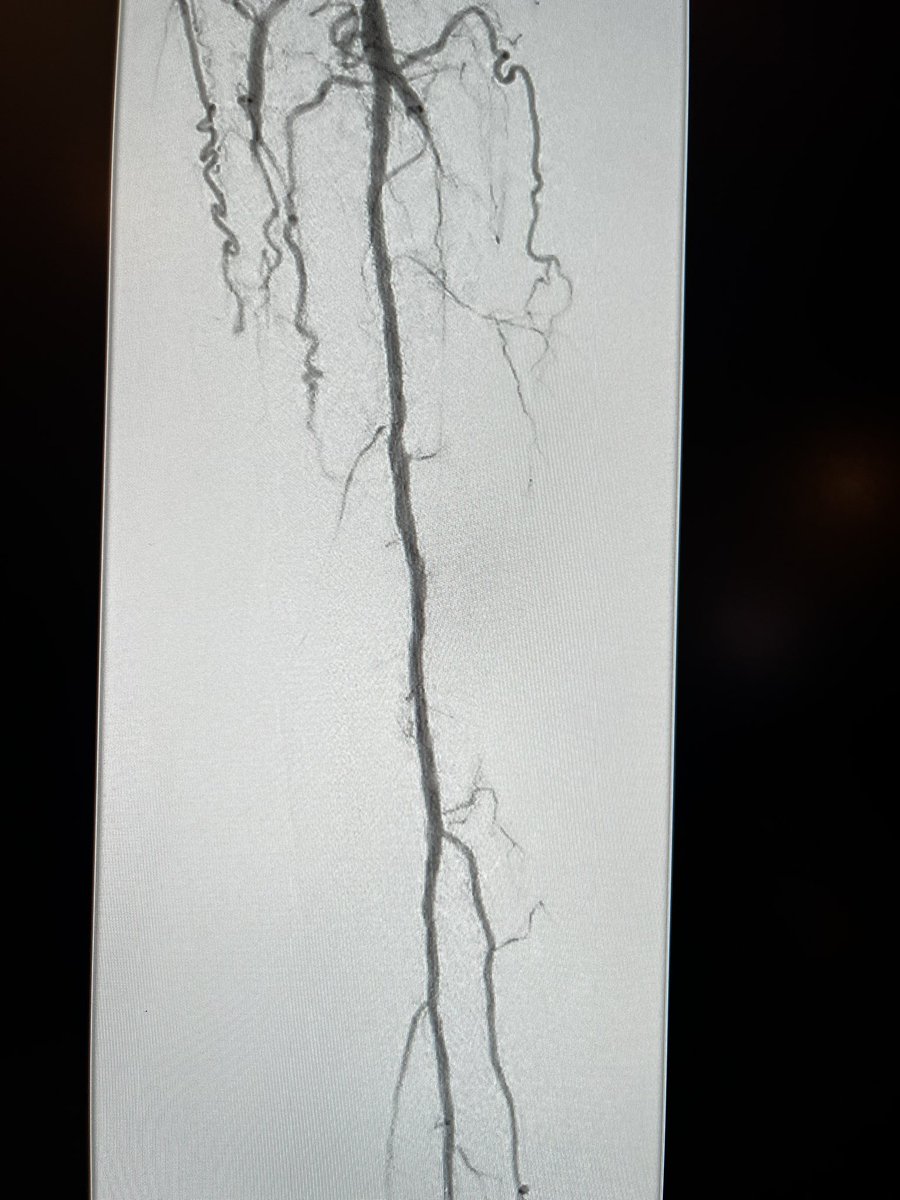

Xing occluded #BTK vessels w amplatz .035 / quickcross .035 helps maintain true lumen and quickly cross BTK CTO. @Abd_Alrifai @tlevin @chadialraies @RilioRiliol @DeanFerreraDO